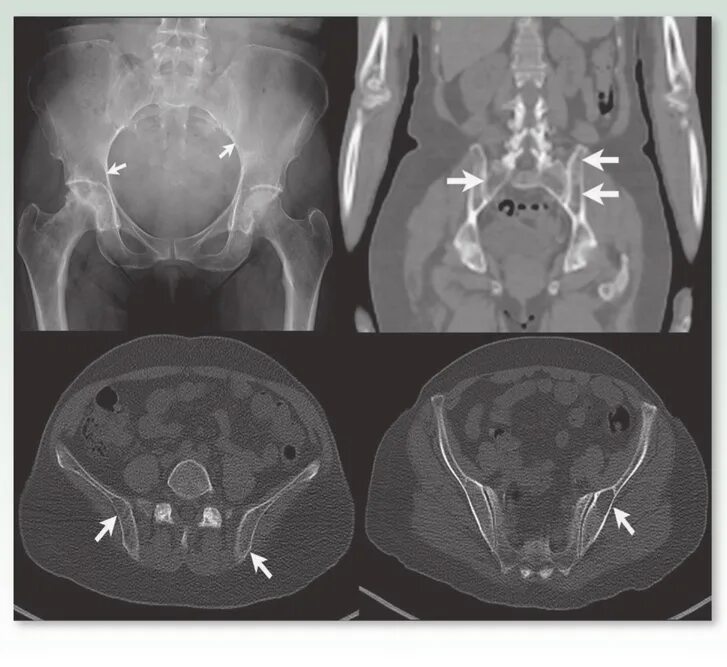

Сакроилеит на кт